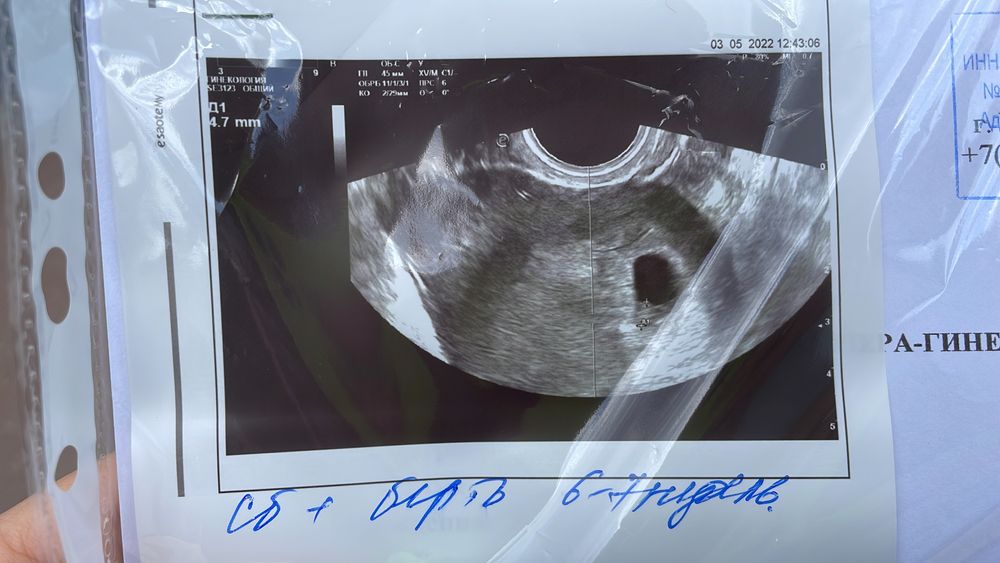

Сердцебиение + Беременность 6-7 недель

В самом темном кружочке ваша крошка. Беременность 6-7 недель, сердцебиение есть Очертания малыша вы на таком снимке не увидите, ни можете в интернете посмотреть как они выглядят на таком сроке или может более четкое узи другого человека найдете

Есть эмбрион, желточный мешочек и плодное яйцо. Сердечко бьется. Подтверждённая беременность 6-7 недель .